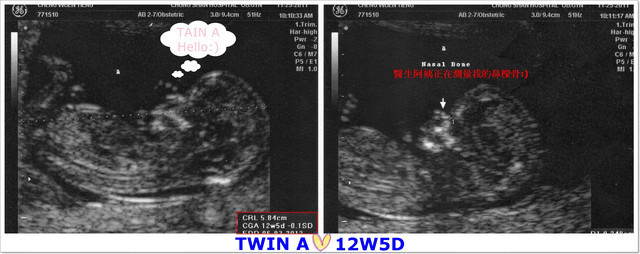

寶貝們週數:12週5天,寶寶們的各個器官持續在發育,

A寶寶身長:5.84公分(比一般值還大) 心跳:158/分

B寶寶身長:5.97公分(比一般值還大) 心跳:160/分

這項檢查花了快一個小時的時間,以往照超音波大概都只花不到10分鐘就結束,

通常都只量了寶寶的身長,確定寶寶們心跳之後就結束,這次的檢查非常非常的仔細,

超音波醫生非常仔細的從寶寶們的頭圍、鼻梁骨角度、手臂和大腿骨長度、腦部發育狀況、

臍帶血流,心跳的頻率,還有媽咪的子宮動靜脈及子宮頸長度等等,都一一仔細的檢查,

連寶寶們的手指頭和腳指頭也都是一根根的數給我們聽哦!

大家一邊盯著螢幕一邊數著寶寶們的手指頭,1~2~3~4~5的數著真是有趣!

而且在測量的期間,醫生每說一句:很好,正常!我和老公就鬆了一口氣(呼)

接著,就讓大家看看寶寶們吧:)

大約作了數十項的檢查之後,

才到了最後的重點-「頸部透明帶厚度檢驗」,

這個透明帶需要寶寶呈現自然平躺的姿勢才能測量得到哦!

寶貝們很乖的,很快的就讓醫生測量到,

只有B寶寶比較頑皮,一直貼著羊膜,醫生不斷的又揉又震動我的肚子,

希望寶寶可以乖乖的躺好,果然寶寶在躺下來的時候後頸部出現一條黑色的帶子,

就是要測量這條帶子的厚度,要是太厚(超過3mm)就表示有唐氏症的危險哦!

呼~還好!最後測量的數值在標準範圍之內!

今天檢驗出來結果,每一項都是正常的,真是太好了((開心ing))